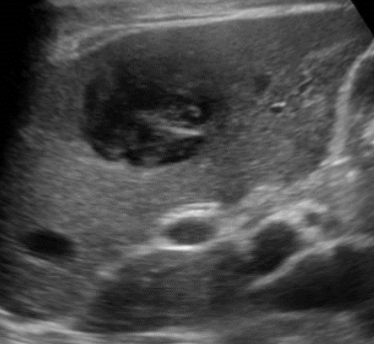

Hydatid Disease/Echinococcal Cyst → infectious, parasitic disease (tapeworm) in sheep-herding areas

clinical hx:traveled recently to sheep herding area (

s/sx: may be asymptomatic, RUQ pain, leukocytosis (if it ruptures)

2D US: water lily sign (infolding from collapsed wall), cyst w/ daughter cells, outer wall calcifications,

color doppler: avascular

DDX: amebic abscess, pyogenic abscess